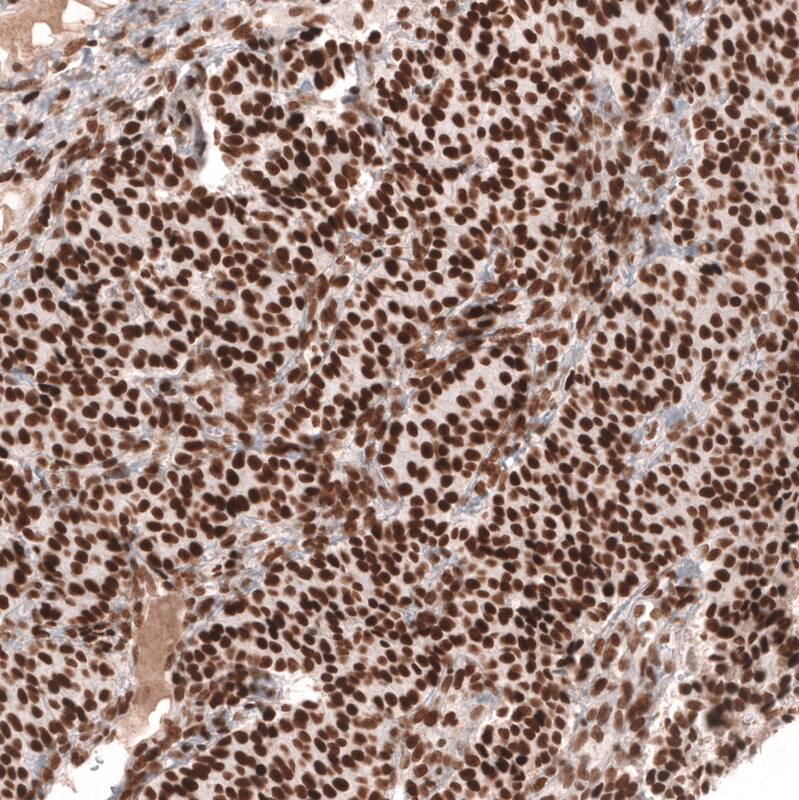

Staining of human lymph node shows strong nuclear positivity in germinal center cells.